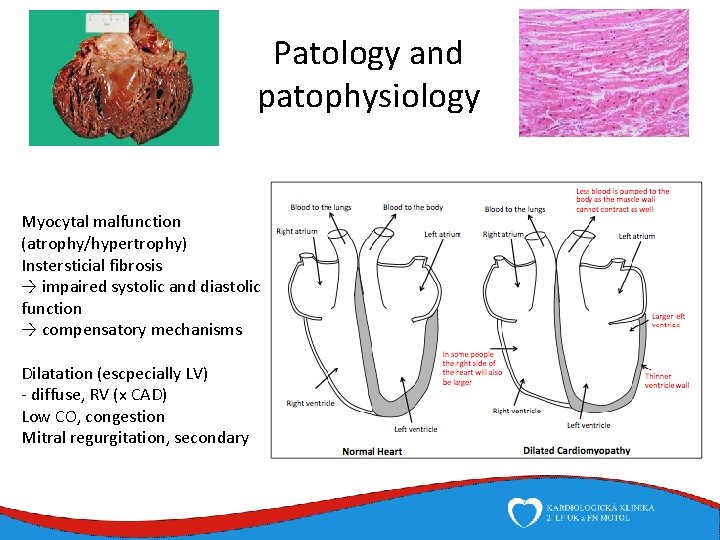

Patology and patophysiology Myocytal malfunction (atrophy/hypertrophy) Instersticial fibrosis → impaired systolic and diastolic function → compensatory mechanisms Dilatation (escpecially LV) - diffuse, RV (x CAD) Low CO, congestion Mitral regurgitation, secondary